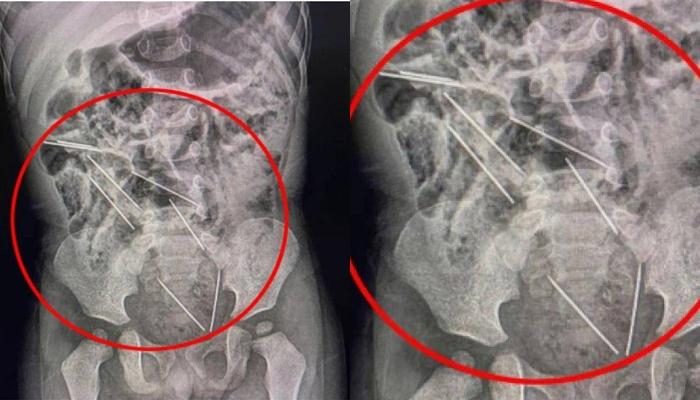

Pantas Dokter Syok Lihat Hasil Rontgen Bayi 2 Tahun ini, Ternyata Ditemukan 8 Jarum di Perutnya

Benar-benar ada 8 jarum tersebar di seluruh perut. Ada 2 di sisi kanan peritoneum, 3 di kiri, 1 di dinding perut, dan 2 di antara area perut.